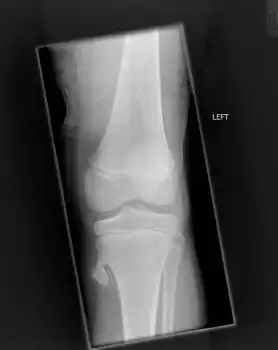

Osteochondroma arising from the large long bone of lower leg, near the knee